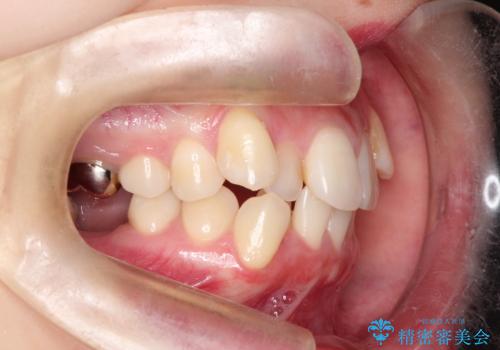

- 患者様は、下顎両側の第1大臼歯(6番)と右上6番の欠損を主訴に来院されました。

通常であればインプラントによる補綴が第一選択となる症例でしたが、患者様ご自身がインプラントを希望されなかったため、矯正治療によって欠損部の閉鎖を図る方針としました。

同時に、親知らず(智歯)の萌出や位置も考慮し、咬合全体のバランスを改善する矯正治療計画を立案しました。